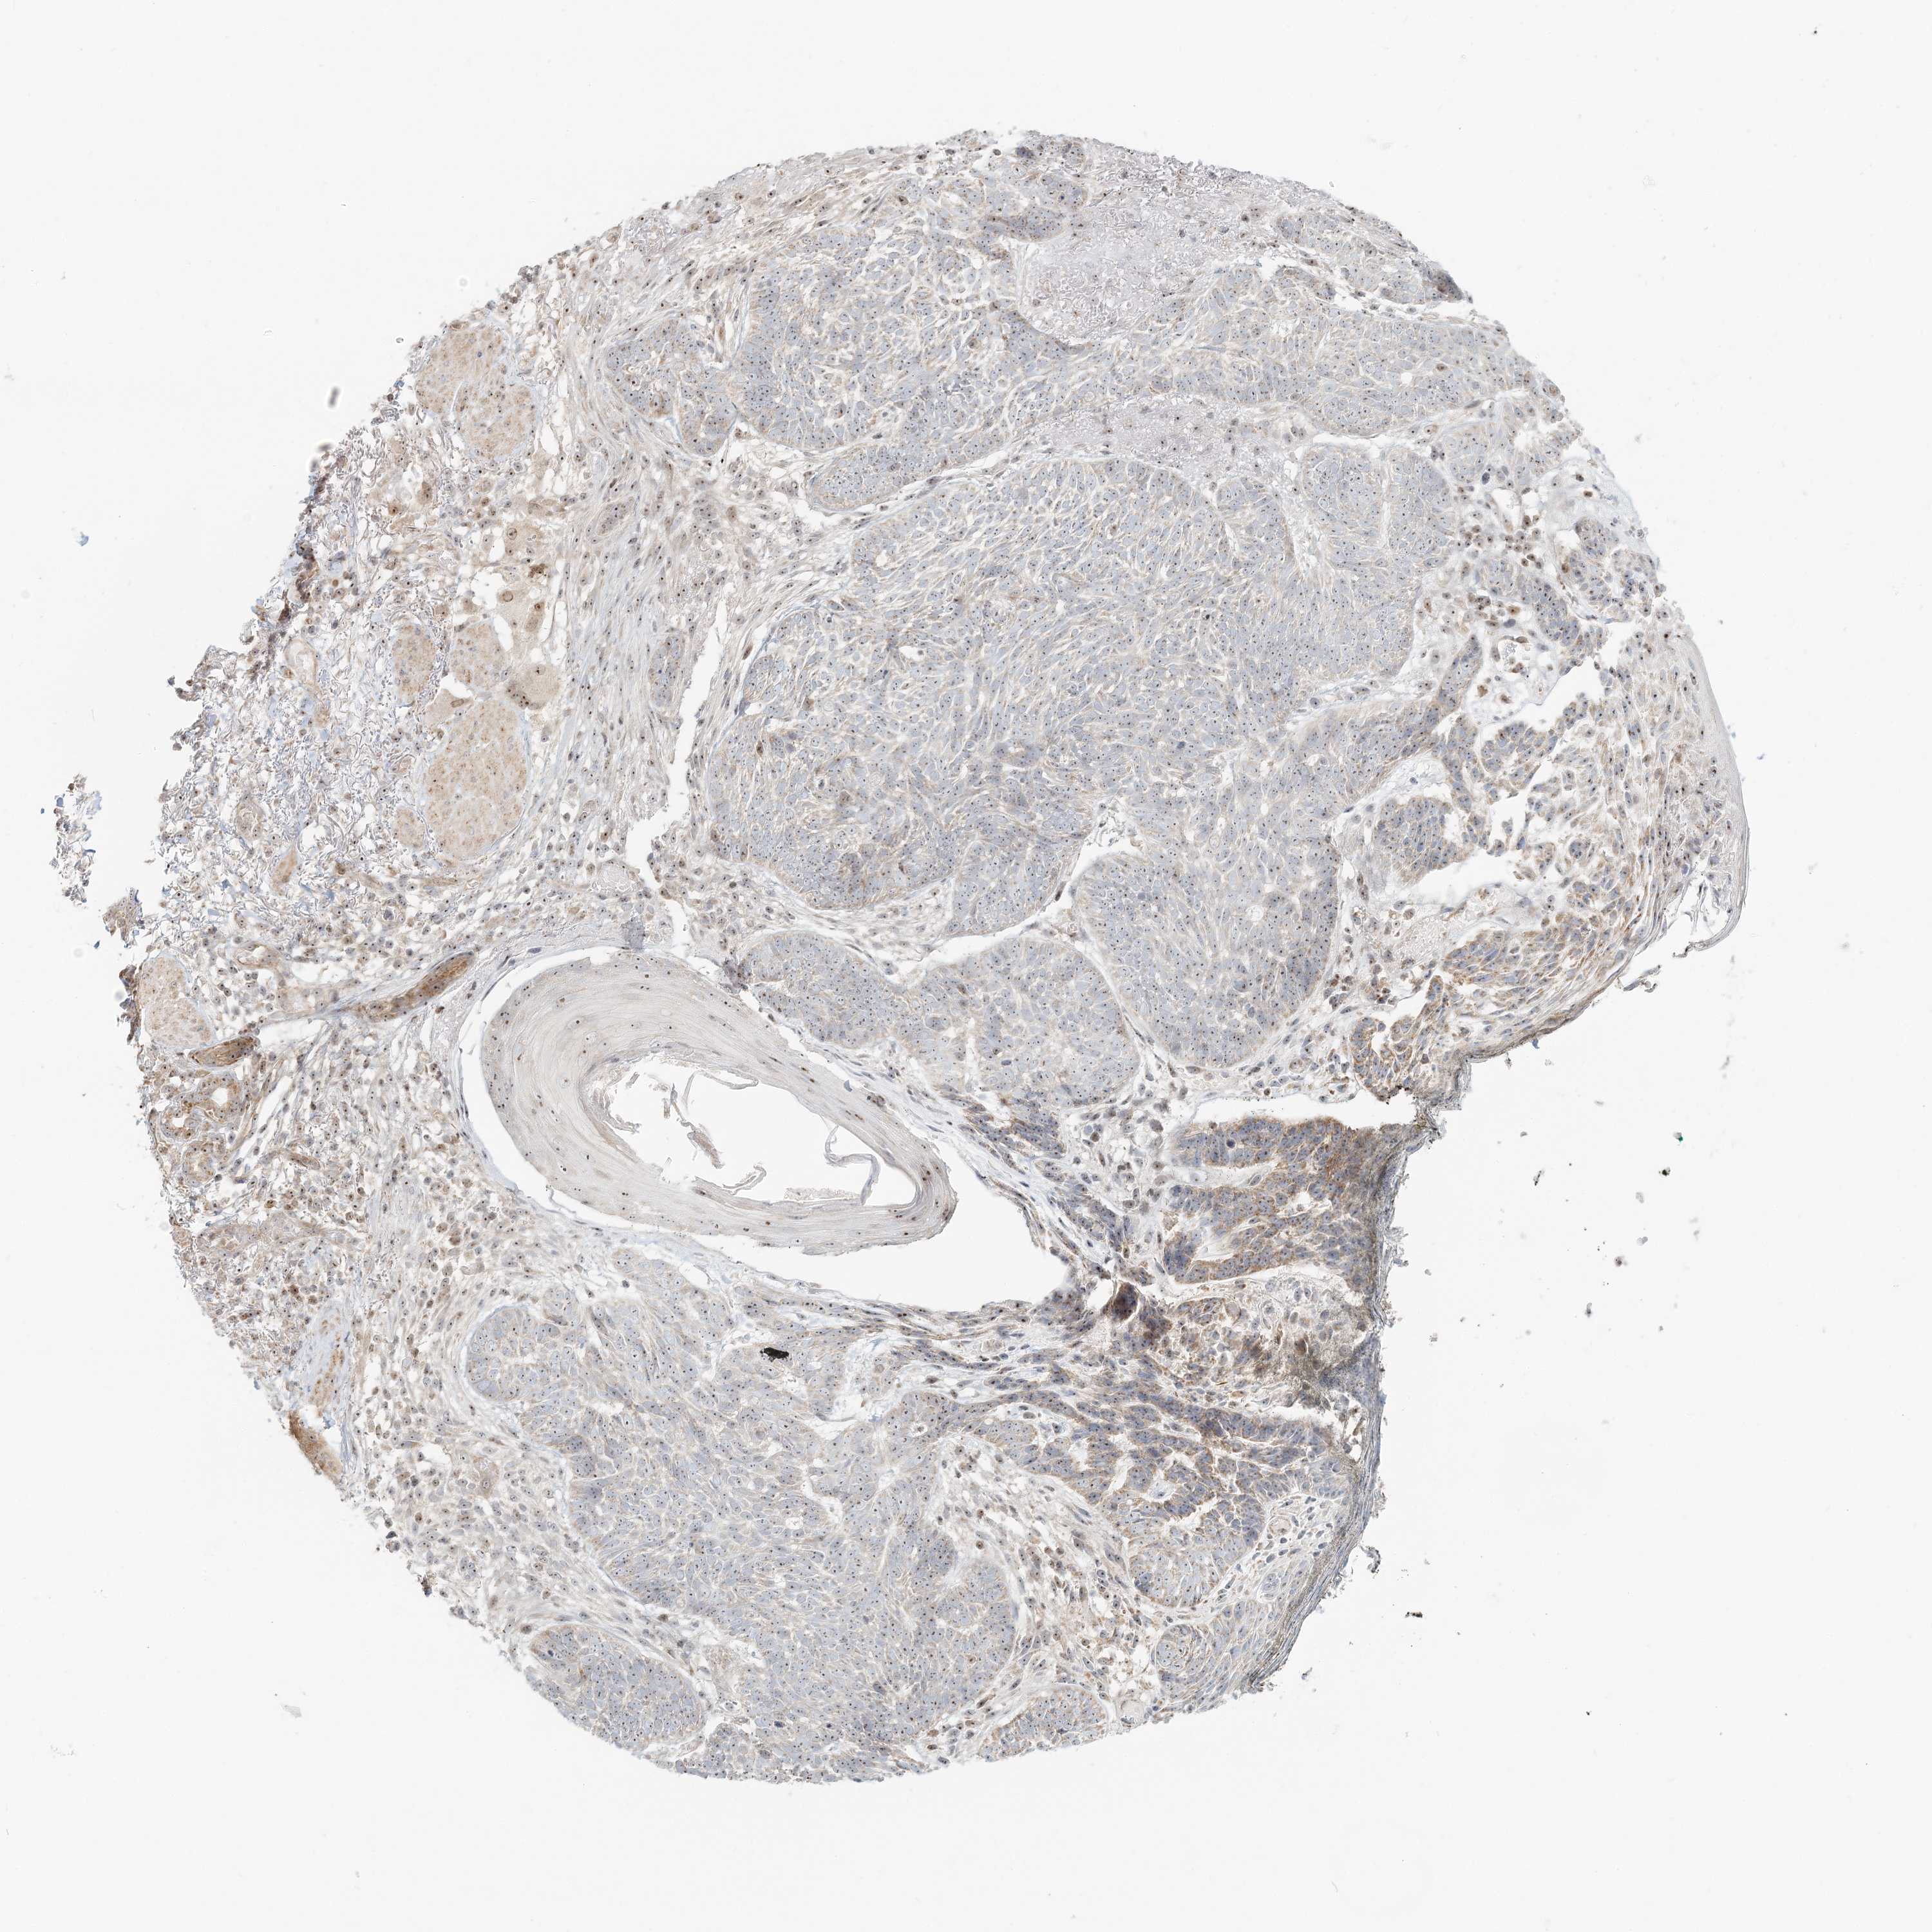

Basal cell and squamous cell cancer

SKIN CANCER - Protein expressioni

A mouse-over function shows sample information and annotation data. Click on an image to view it in a full screen mode. Samples can be filtered based on level of antibody staining by selecting one or several of the following categories: high, medium, low and not detected. The assay and annotation is described here.

Antibody stainingi

Antibody staining in the annotated cell types in the current human tissue is reported as not detected, low, medium, or high, based on conventional immunohistochemistry profiling in selected tissues. This score is based on the combination of the staining intensity and fraction of stained cells.

Each image is clickable and will lead to virtual microscopy that enables deeper exploration of all samples and also displays staining intensity scores, fraction scores and subcellular localization as well as patient and tissue information for each sample.

Antibody HPA037444

Staining

Not detected

Intensity

Negative

Quantity

None

Location

Basal cell carcinoma

Squamous cell carcinoma, NOS